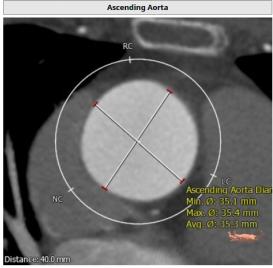

CT:

主动脉瓣Type 0型二叶瓣,瓣叶瓣缘结节样增厚伴中度钙化,开放受限。冠脉高度可。法式窦结构可,心脏角度约52°,左室较小,升主动脉未见明显扩张,右股动脉直径大于5.5mm,可作为主入路。患者为中度钙化的,重度主动脉瓣狭窄,呈鱼嘴型,结合主动脉根部结构,考虑植入Sapien 3瓣膜。

窦管结合部

升主动脉